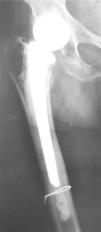

Presentamos el caso de una mujer de 83 años con antecedentes de osteoporosis, posmenopáusica en tratamiento semanal con bifosfonatos y aporte diario de calcio y vitamina D y fractura de cadera derecha a los 64 años, intervenida con colocación de prótesis cementada. Acudió a consulta por coxalgia derecha mecánica, con claudicación en la marcha de meses de evolución. En la exploración destacaron limitación y dolor a la rotación de la cadera derecha. Se realizó una radiografía de cadera (fig. 1) y, ante la sospecha de movilización aséptica de la prótesis, se realizó una gammagrafía ósea en 3 fases que muestra captación en el tercio distal (fig. 2a), confirmando así el diagnóstico. Iniciamos tratamiento con ranelato de estroncio más aporte de calcio y vitamina D. Transcurridos 2 meses, la paciente mejoró significativamente y desapareció la claudicación para la marcha que presentaba con anterioridad. A los 6 meses se repitió la gammagrafía ósea, que mostró una reducción cercana a la normalidad de la hipercaptación isotópica que mostraba al inicio (fig. 2b).